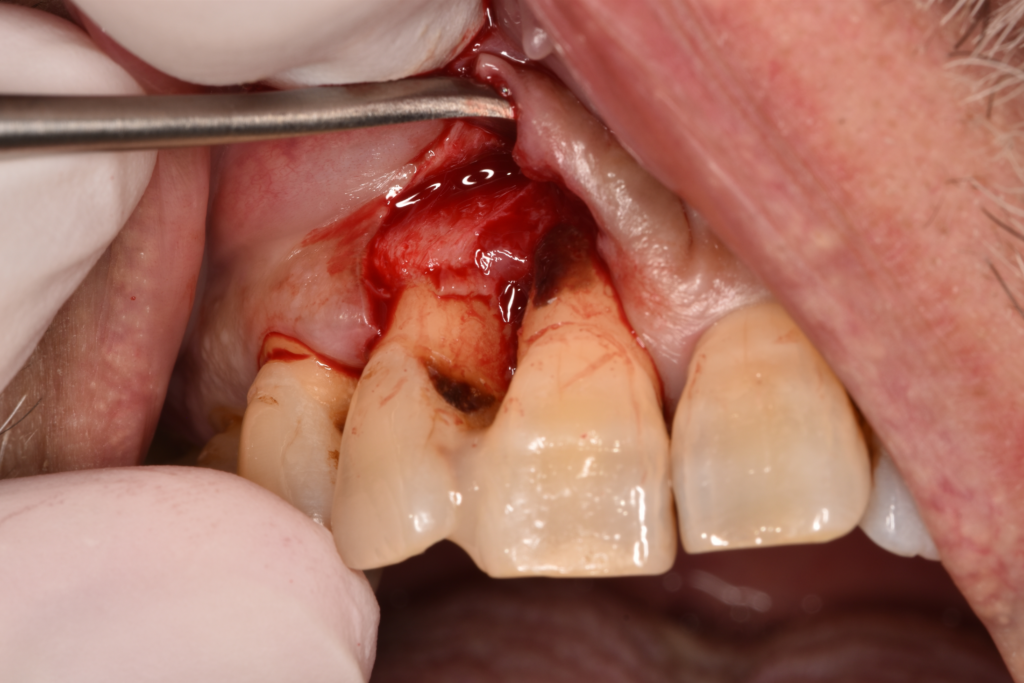

↑レントゲンで骨吸収を認めます。歯肉を切開すると実際に骨がありません。